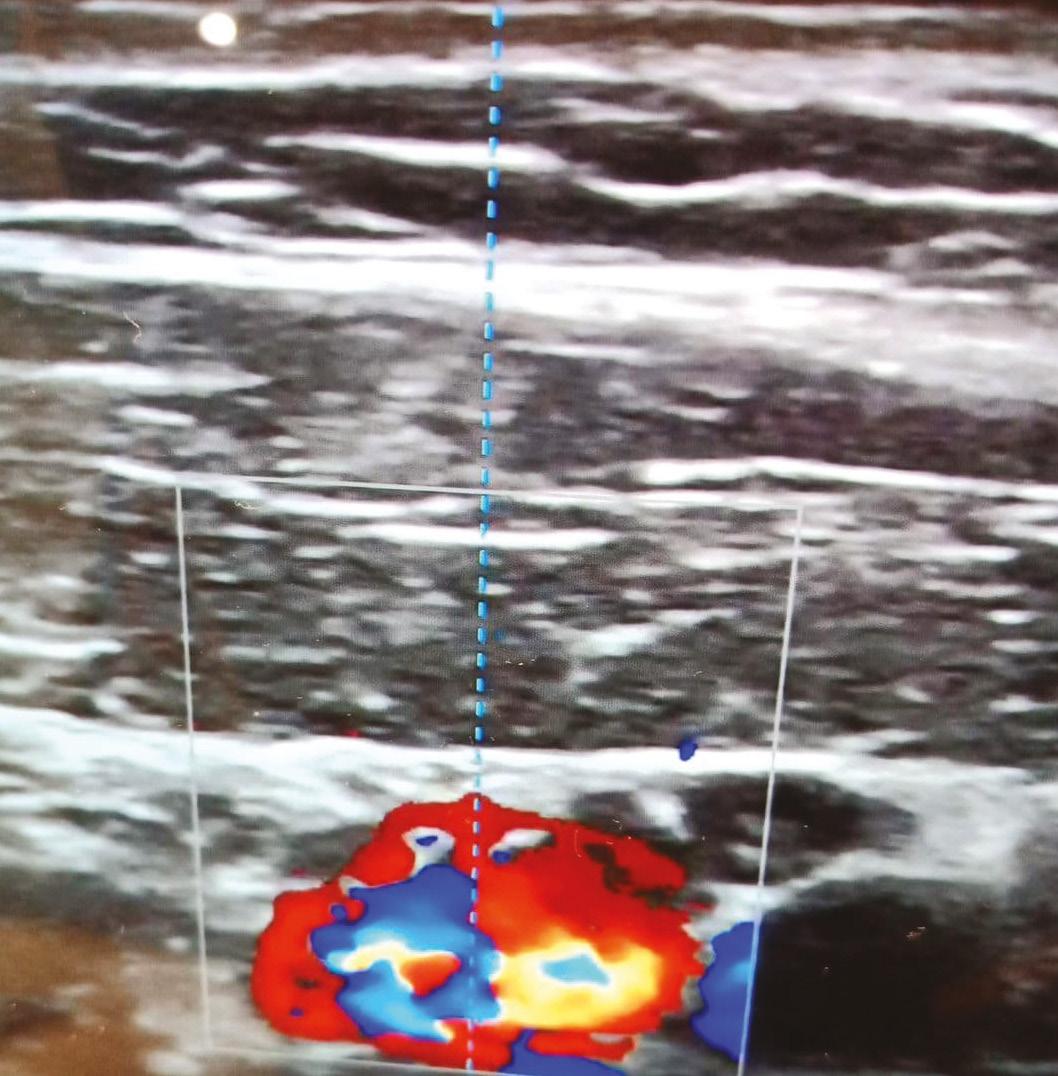

A new foundation ultrasound course launched by aesthetic practitioner Dr MJ Rowland-Warmann will be taking place in December. The two-day Facial Ultrasound for Aesthetic Practice course will cover the basics of ultrasound, the fundamentals of how ultrasound works, recognition of structures in the face often treated with dermal fillers, and the different filler types and complications they can cause. Speakers include aesthetic practitioner and phlebologist Dr Leonie Schelke and dermatologist Dr Peter Velthuis from the Netherlands, consultant orthopaedic surgeon Mr Ansar Mahmood, consultant aesthetic oculoplastic surgeon Mrs Sabrina Shah-Desai, and aesthetic practitioners Dr Steve Harris and Dr Rowland-Warmann. Dr Rowland-Warmann said, “Ultrasound is the future of aesthetic medicine. Rarely has a development come along that will make such a difference to patient safety. Practitioners should recognise how ultrasound can elevate their practice and set them apart as practitioners who care about the safety and welfare of their patients and the accuracy of their results.” The course will take place on December 5-6, 2021 at BMA House in London.

Miss Hawkes notes that while she currently doesn’t use ultrasound in her clinic, it’s something she would like to incorporate in 2022. She comments, “Over the last year or so, I’ve seen how helpful it can be for our industry. At the moment I don’t offer non-surgical rhinoplasties to my patients because of how dangerous they can be in terms of causing blindness, but being able to scan the area prior to treatment would mean that I would be able to carry out this procedure in a safer manner and avoid vessels. In addition, I’ve always thought that there was a big place for treating the glabellar in aesthetics, but this is often shied away from because of the risks involved. Again, the use of ultrasound will be useful for ensuring that this can be done with minimal chance of risk.”

Ultrasound has been a buzzword in aesthetics for a few years now, but it has been within the last 12 months that it’s really emerged as a more common part of aesthetic practice. Consultant plastic and reconstructive surgeon Mr Dalvi Humzah notes that a lot of this can be attributed to the devices becoming more accessible. “I remember four years ago myself, Dr Kate Goldie and Dr Simon Ravichandran did a presentation on how useful ultrasound could be, but we demonstrated it with a huge clunky machine that was so difficult to transport anywhere,” he laughs. “While people liked the presentation and acknowledged it was a good idea at the time, everybody noted the impracticality of expecting clinics to get these massive (and expensive) devices.”

Now, ultrasound technology has developed and practitioners can access it as portable, handheld devices. Mr Humzah comments, “This not only helps with accessibility, but it also means that the price is a lot lower. Before, they would cost clinics upwards of £20,000 and now they’re available for a quarter of the price, which is definitely contributing to the rise in ultrasound use.” Current handheld devices on the market include Clarius and VScan, which Mr Humzah has used in his clinic, while others available include Butterfly IQ, Lumify, and Sonoinject. As an early advocate for ultrasound, Mr Humzah believes that it’s a welcome addition to the specialty’s interest in preventing complications. “Scanning your patients prior to injecting means that you can see their anatomy, identify where the large blood vessels are and therefore plan where your injection points are going to be. This helps to minimise the risk of complications, such as causing a vascular occlusion. It can also help to monitor the outcomes of the treatment and help treat complications,” he notes. For more information on the benefits of ultrasound, you can read Introducing Ultrasound to Your Clinic by Dr Kim Booysen on the Aesthetics website.1

Although there has already been a growth in popularity for ultrasound, Mr Humzah notes that there is still a long way to go. “Most ultrasound devices, although useful, have not been

developed specifically for the aesthetics specialty. Rather, they have been designed for general healthcare, and we have been able to apply these to aesthetics,” he says. “So, I think the next step for ultrasound use in aesthetic medicine is working with companies to get ultrasound technology that is really tailored to aesthetics, and I’m currently in talks to get the ball rolling. My hope is that in the next 12 months we can expect to see ultrasound technology that is more aesthetics-friendly.” In order for people in the industry to further understand ultrasound, Mr Humzah adds that it’s important for practitioners to attend courses on the topic, something which his training academy will be offering next year, one of several new courses starting to emerge. “The only way for ultrasound to evolve is if more people have knowledge on the subject, and more people are discussing it and using it,” he adds.